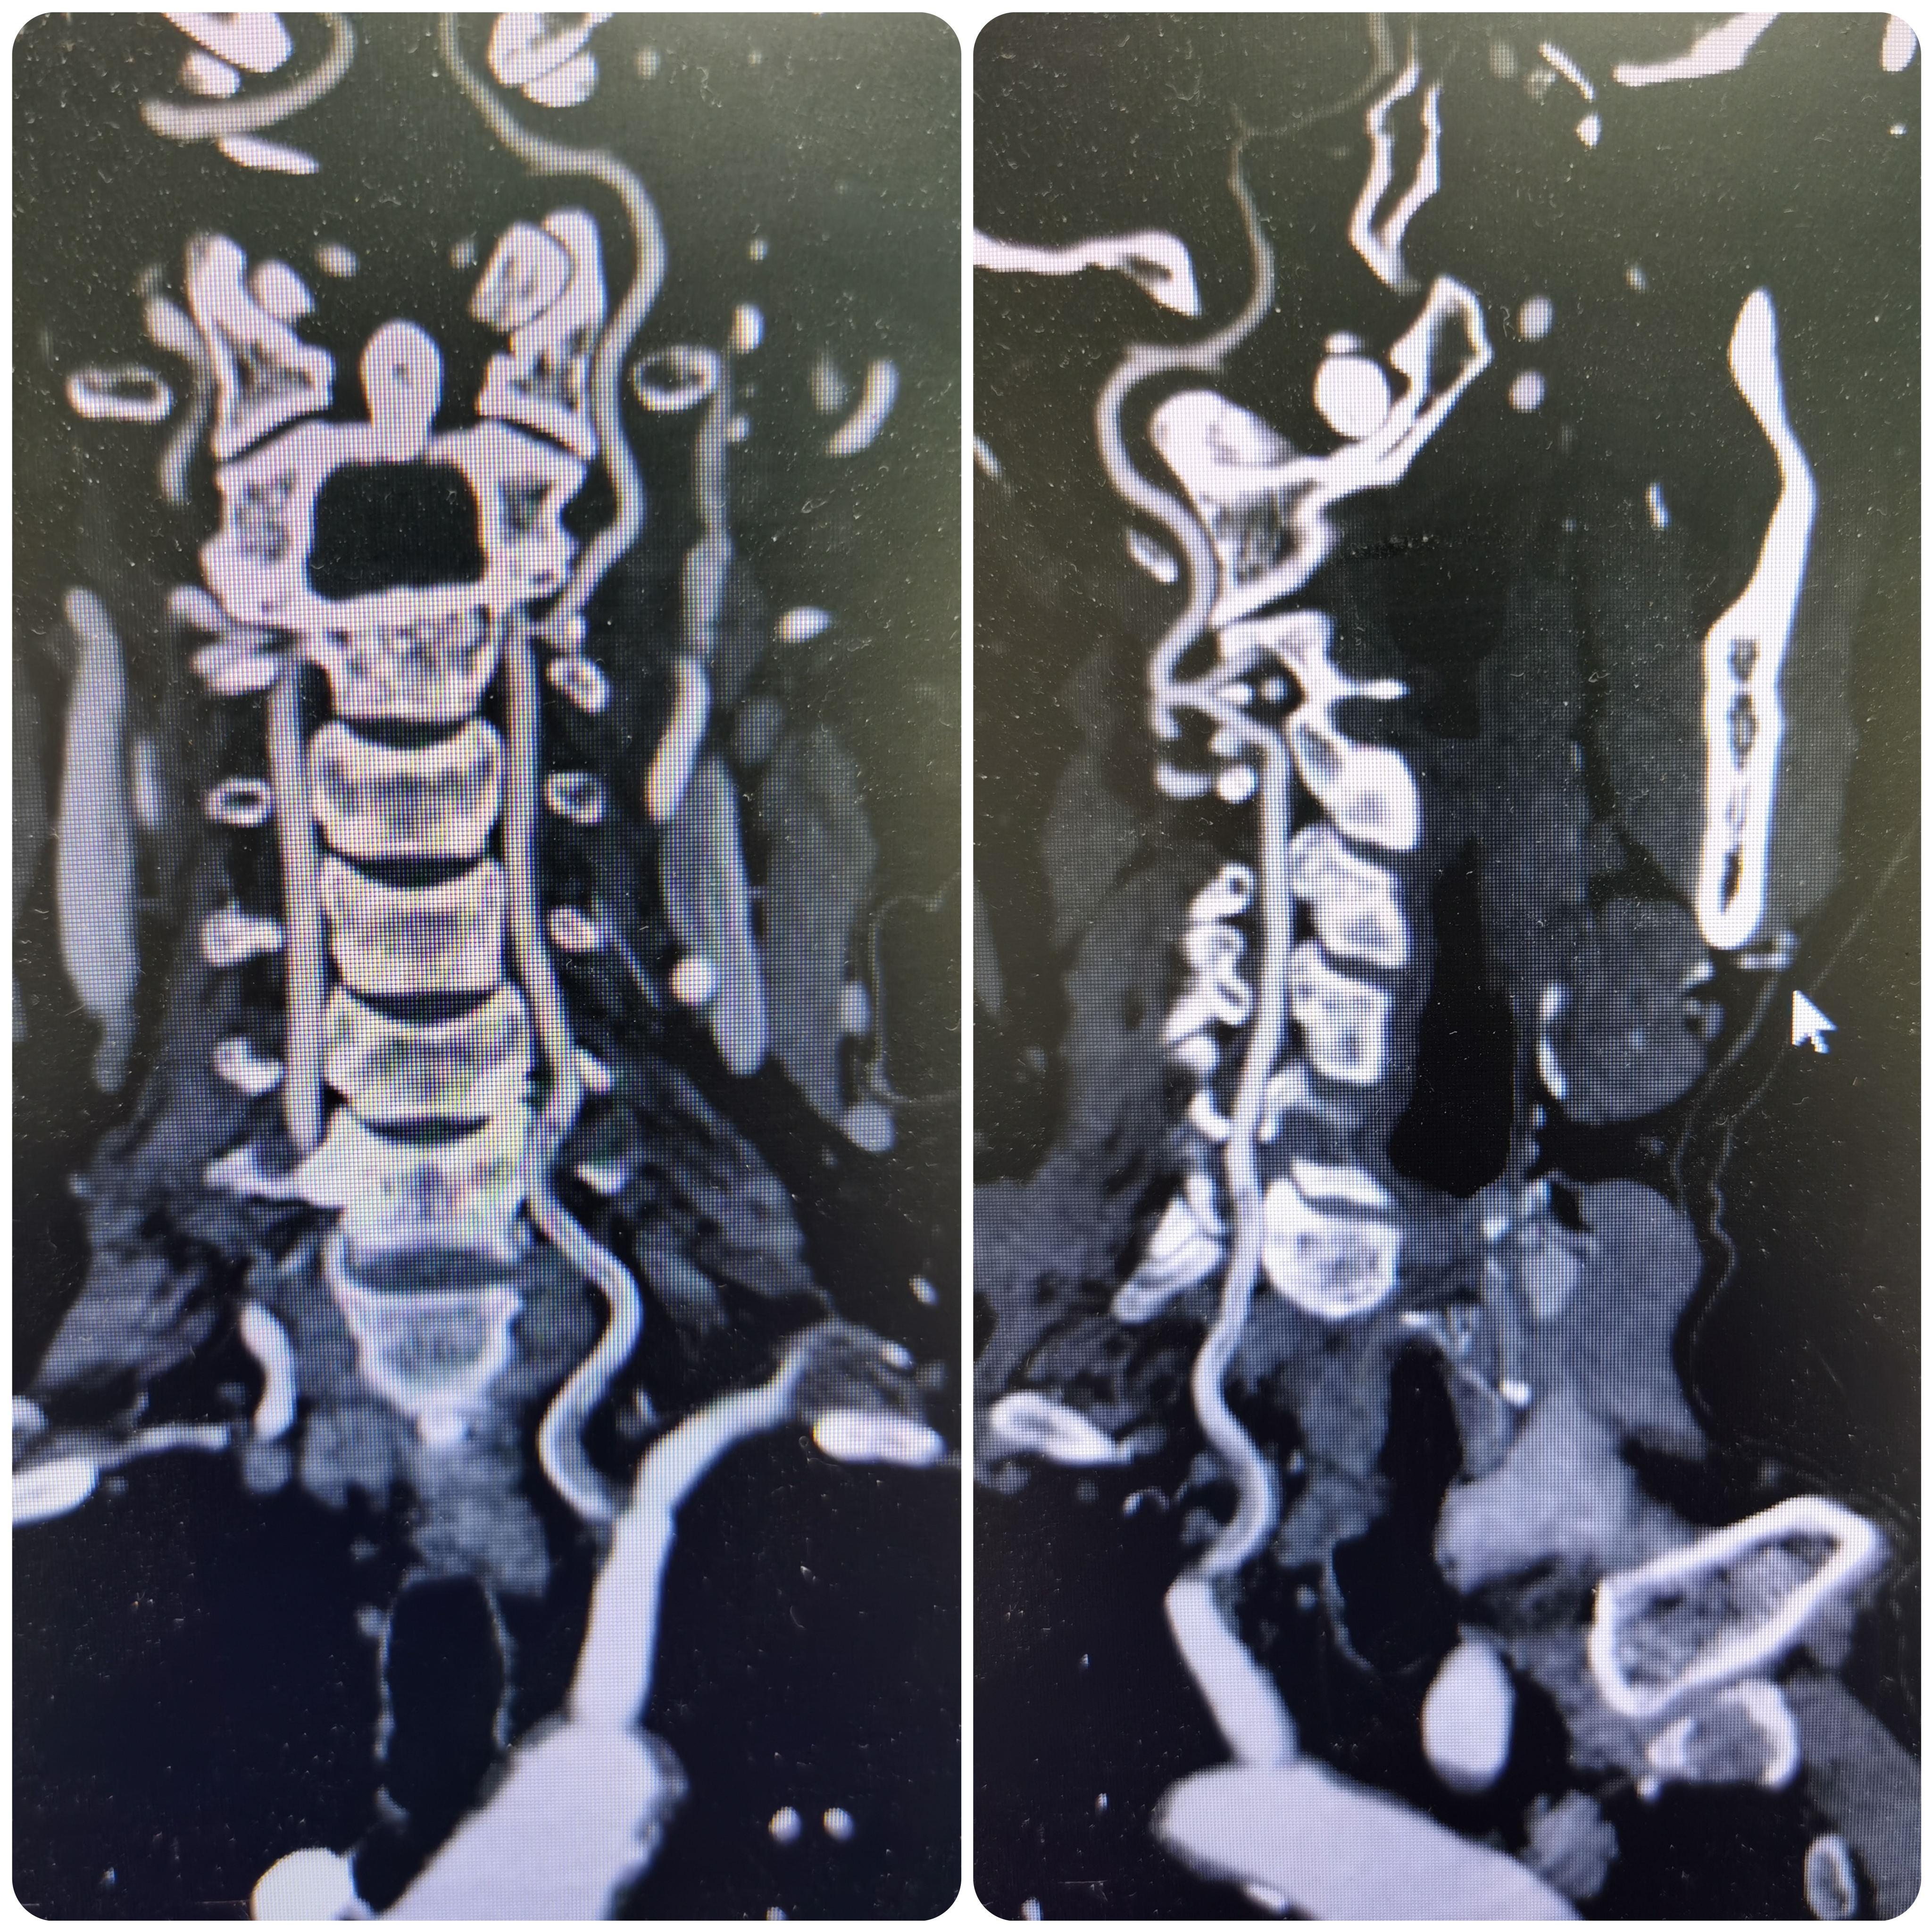

2、CTA证实左椎动脉起始部重度狭窄合并血栓,系责任血管,存在急性闭塞或残存血栓脱落至基底动脉风险,需积极处理。